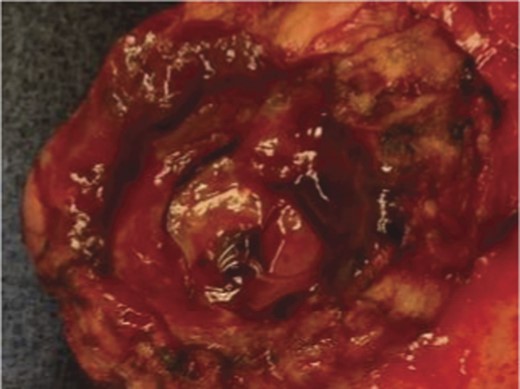

A frail 77-year-old multiparous Caucasian female with a history of aspirin and naproxen use, presented to an outside hospital with epigastric pain and an episode of hematemesis. She had no prior history of peptic ulcer disease, alcoholism or pancreatitis. The patient was hemodynamically stable with an acute anemia (hemoglobin of 7.7 g/dl), which prompted transfusion of 2 units of PRBC and transfer to a tertiary care facility. Upon transfer, she underwent an emergent upper endoscopy, which revealed a large amount of blood with clots in the lumen of the stomach. However, sufficient suctioning of the large intra-gastric clots was not possible; hence, an underlying etiology was not obtainable. The patient subsequently underwent a diagnostic angiography, which revealed a 4 cm mid-SA pseudoaneurysm with active contrast extravasation into the stomach which can be seen in Figs 1 and 2. The radiologist decided to perform a transcatheter arterial coil embolization of the artery to halt the active bleeding. A post procedure angiography revealed no further contrast extravasation. A planned upper endoscopy was repeated the following day that revealed some residual clotted blood in the stomach, no active bleeding and a deep 4 cm gastric ulcer. Due to the high risk of re-bleeding, the patient was optimized physiologically and consented and prepared for exploration. Intraoperatively we observed that the SA pseudoaneurysm was densely adherent to the posterior wall of the stomach, and coursing through an inflamed distal pancreas. We decided to proceed with an en bloc resection of SA pseudoaneurysm, distal pancreatectomy, partial gastrectomy and splenectomy. After the celiac axis was surgically defined, proximal and distal SA controls were obtained and a circumferential posterior gastrotomy was made. There was a visible posterior gastric mucosa to splenic arterial fistula, with the radiologically inserted embolic coils clearly visible. This can be seen in surgical specimen (Figs 3 and 4). Once the stomach was reflected, the splenic vessels and the pancreas were divided and the specimen removed. The pathology reports indicated active gastritis with transmural ulceration into the splenic artery (SA) and adjacent pancreatic tissue. No malignant cells were identified in the gastric or pancreatic tissue and the SA was not aneurysmal (Fig. 5). During the postoperative period, the patient had an uncomplicated recovery and was discharged on day 5.

Surgical specimen of en bloc partial gastrectomy, distal pancreatectomy and splenectomy.

Surgical specimen of en bloc partial gastrectomy, distal pancreatectomy and splenectomy. Embolic coils visible in arterial lumen.